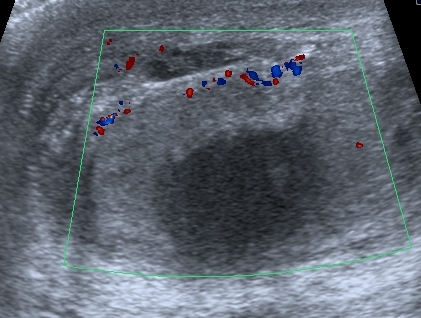

Сегодня смотрел его на контрольном УЗИ: в правой половине мошонки - небольшое количество жидкости. Яичко прежних размеров, кровоток в яичке востановился,

но определяется в основном в подоболочечной зоне

- I20111124163305453.jpg (104.41 КБ) 1676 просмотров

В области ворот яичка - гипоэхогенный участок с нечёткими контурами.

Пациент выписался домой, пока на контроль не появлялся. Через три дня после операции кровоток в яичке был достаточно "живой", нерестриктивный (см. скан с триплексом), но большое сомнение оставил приличный по размерам гипоэхогенный участок. Да и анамнез - около двух дней без кровотока... Во время операции хирурги делали пробу - надсекали оболочку яичка - получили капилярное кровотечение, на основании чего заключили, что яичко жизнеспособно. Я про такую методу , честно говоря, не слышал, дай Бог, чтоб эта проба работала.